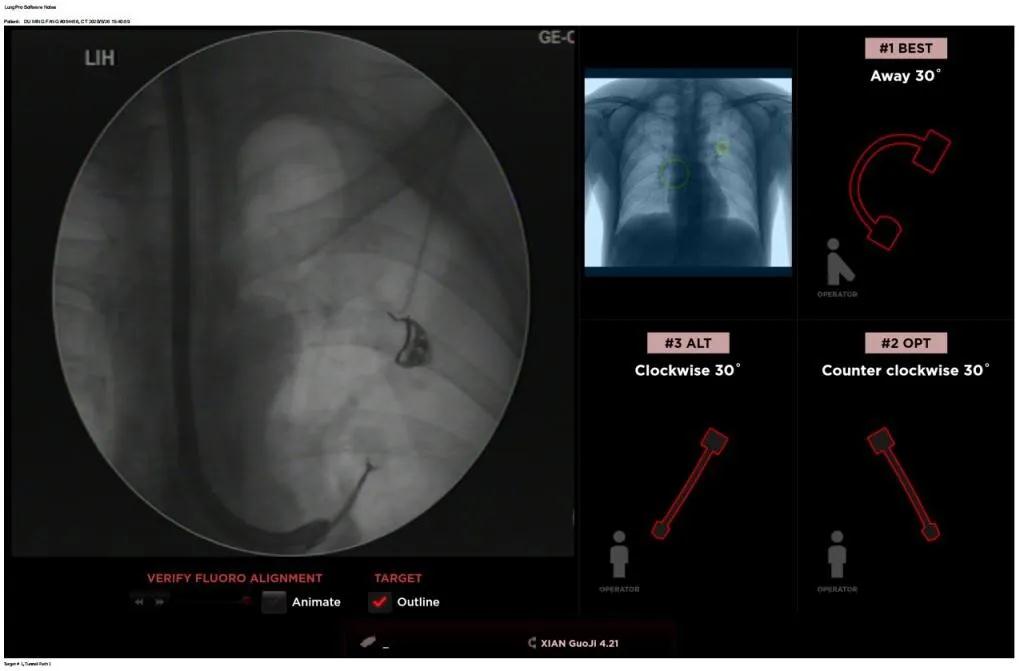

經(jīng)過充分的討論后,歐陽海峰副院長決定為患者實施LungPro全肺導(dǎo)航系統(tǒng)引導(dǎo)的經(jīng)支氣管跨肺實質(zhì)肺外周結(jié)節(jié)活檢術(shù)。Broncus導(dǎo)航系統(tǒng)LungPro具有全球領(lǐng)先獨創(chuàng)的BTPNA技術(shù)(支氣管鏡下跨結(jié)節(jié)抵達(dá)術(shù)),可以實現(xiàn)對氣道外周孤立性肺小結(jié)節(jié)的精準(zhǔn)定位,建立直接通往氣道外病變部位的通道,以實現(xiàn)全肺的診斷及后續(xù)治療。這項技術(shù)不僅彌補(bǔ)了現(xiàn)有支氣管鏡技術(shù)由于受限于病變部位是否有氣道可通向以及無法準(zhǔn)確定位病變部位而造成的較低診斷率,同時還彌補(bǔ)了CT引導(dǎo)下經(jīng)胸穿刺(TTNA)無法適用于某些特定部位如中央及肩胛骨等結(jié)節(jié)的問題,并且還避免了經(jīng)胸穿刺給患者帶來氣胸、出血的高風(fēng)險,可有效提高肺部結(jié)節(jié)及早期肺癌診斷陽性率,亦可用于早期肺癌的射頻消融或微波治療,具有微創(chuàng)、安全、同期雙肺診療等優(yōu)勢。